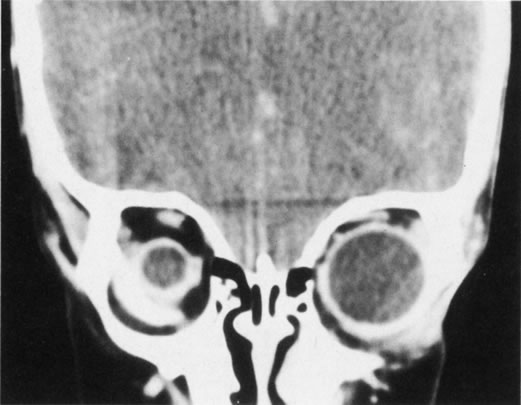

Hypertelorism is often associated with a variety of facial clefts, craniosynostosis, and meningoencephaloceles. The normal distance between the orbits is roughly 16 mm at birth and increases to 25 to 28 mm in adults.15 A widening of the anterior ethmoid air cells is believed to be the main anatomic defect responsible for primary orbital hypertelorism, resulting in an increase in soft tissue, bone, and cartilage between the medial canthi.16 The posterior ethmoid air cells and the sphenoid bone are usually normal, and as a result, the optic foramina are usually normal as well. The cribriform plate is not widened but can be depressed 10 mm below its usual level, making the extracranial approach to the correction of this defect hazardous. The angle between the central axes of the orbits is normally 45°. In orbital hypertelorism, the axes of the orbits are more divergent, measuring up to 60° in severe cases.

Surgical correction of hypertelorism usually entails a combined intracranial and extracranial approach. All four walls of each orbit are osteotomized to free them from the frontal, zygomatic, maxillary, nasal, and sphenoid bones. The excessive intervening tissues are removed, and the orbits are brought closer together in the midline. The resultant bone gaps are filled with bone grafts.